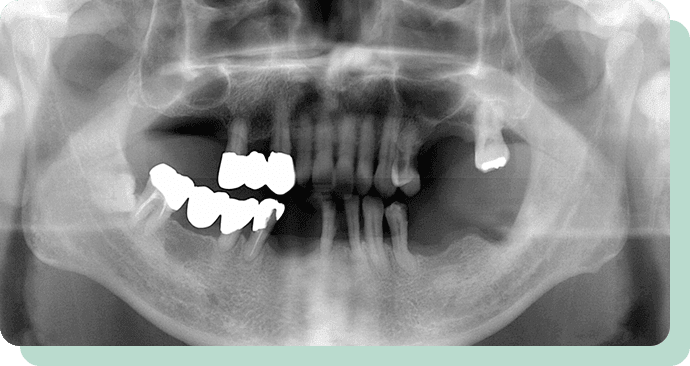

根面にキャップをかぶせて入れ歯に取り込んでいくことで、入れ歯の安定度を増すことが可能です。

処置前後

左の写真は、歯周病が進んで、どんどん歯が抜けていっている状態です。

この方は、歯を短くし、金属のキャップの上に特殊な入れ歯を装着。

これにより、快適にお食事ができるようになりました。